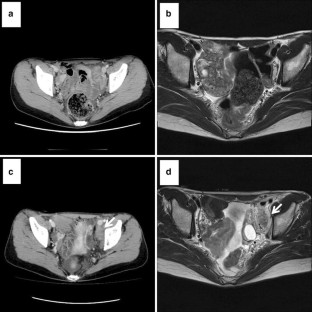

Fig. 1

Fig. 2